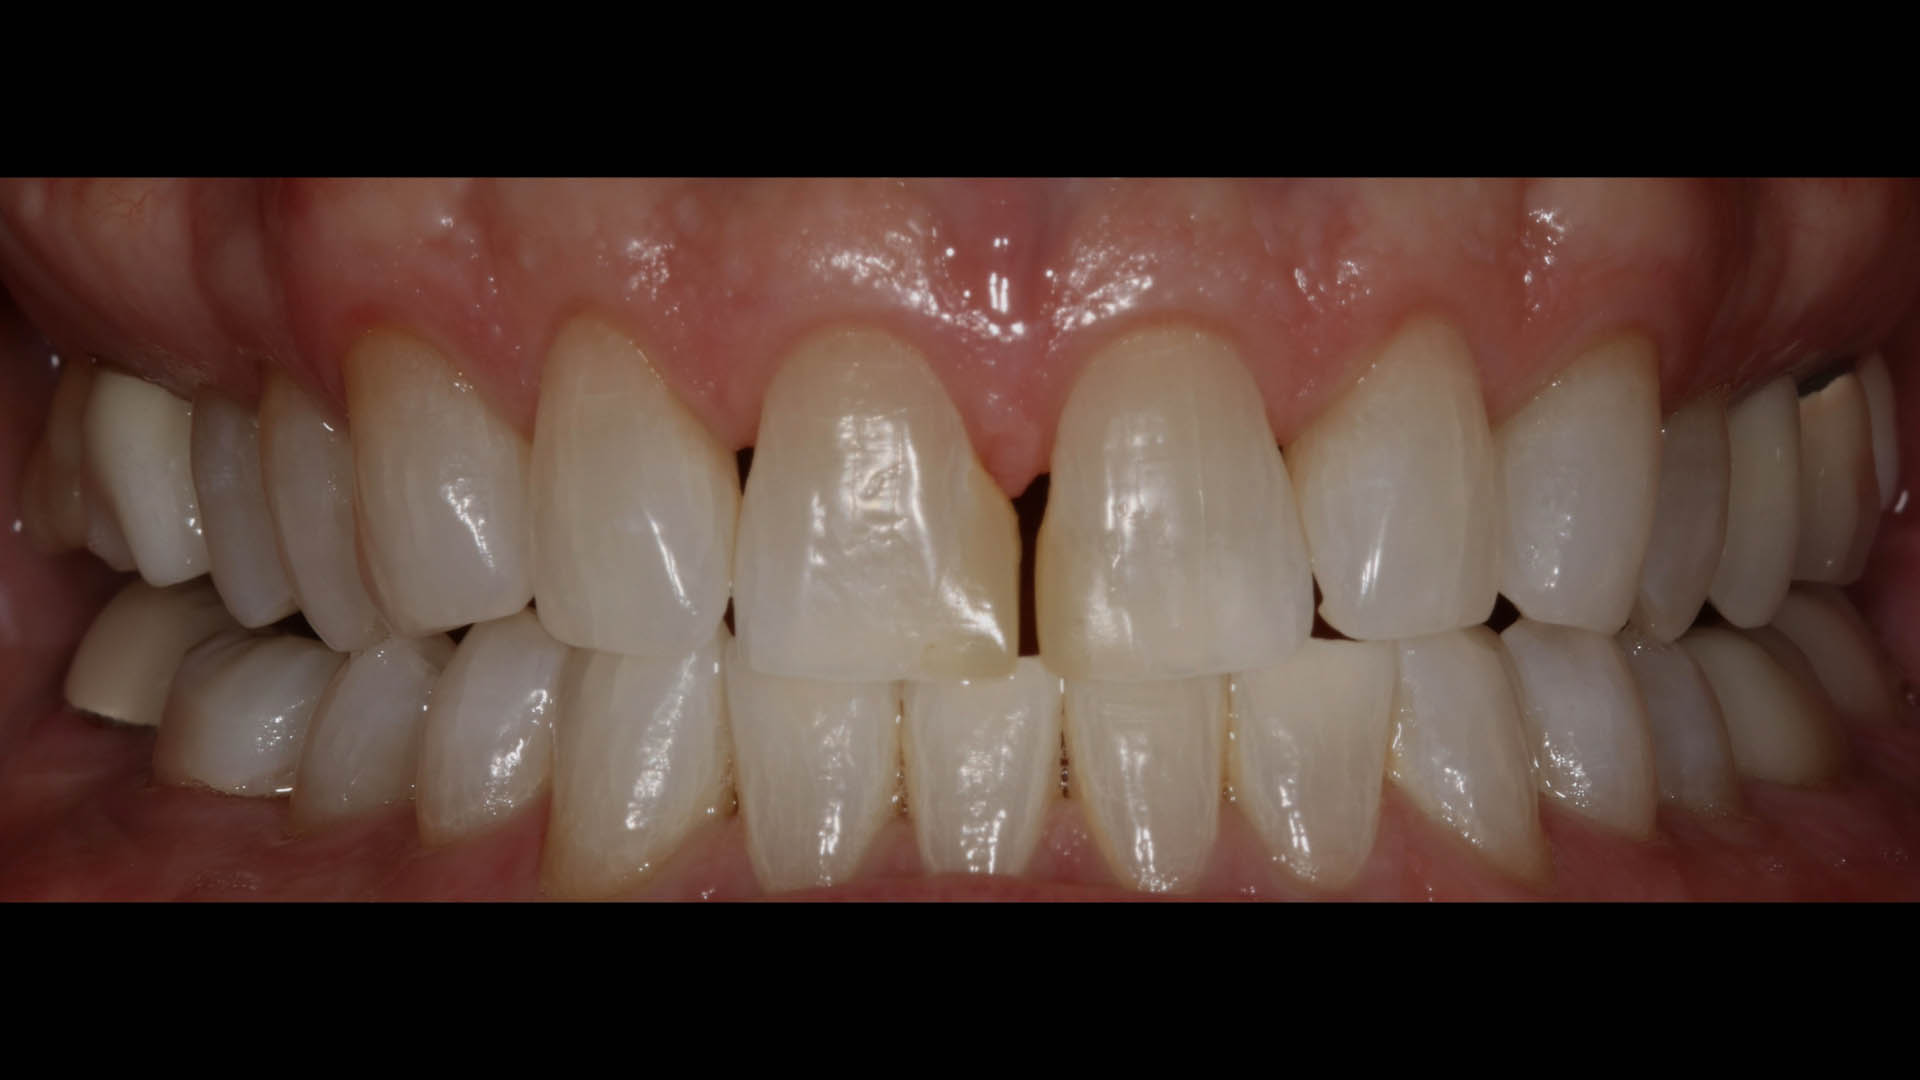

Take a glimpse into the magic of Coral Gables Dentistry through our before and after pictures. See firsthand the incredible smile makeover transformations that have brought confidence and joy to our patients.